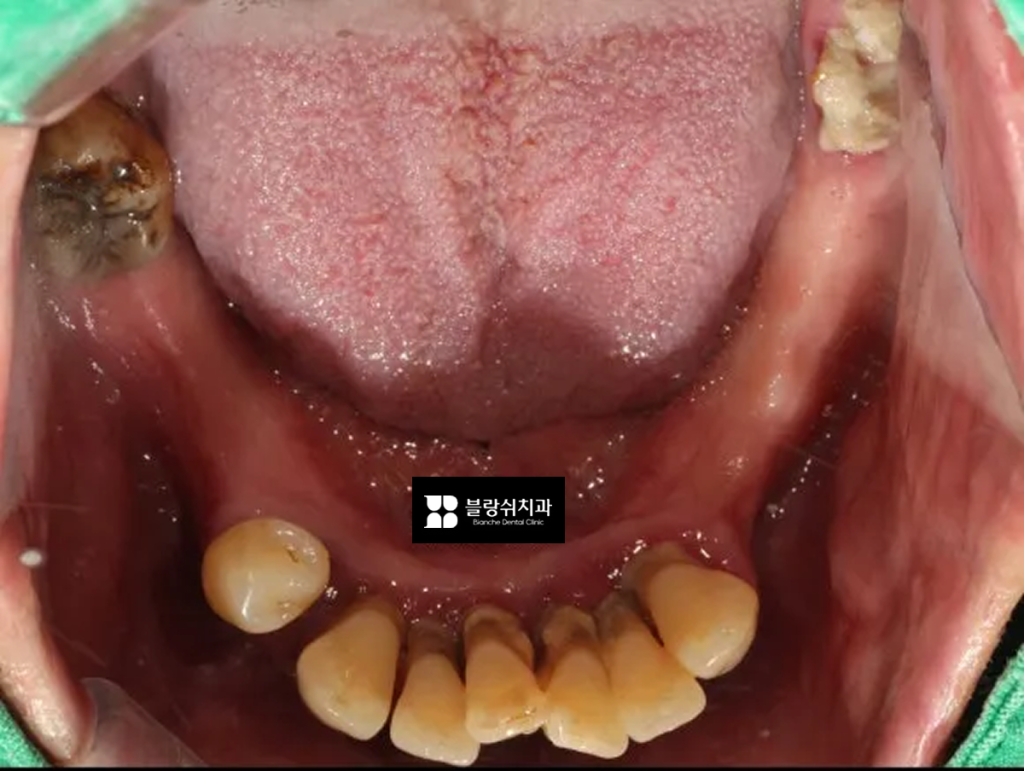

이 환자분은 아래턱 잇몸뼈가 부족한 상태로 내원하셨습니다. 단순히 임플란트만 심기 어려워서 뼈이식이나 치조골을 넓히는 작업이 필요한 상황이었고, 치아 배열이 무너져서 제대로 씹기 어려운 상태였어요.

특히 위쪽 어금니가 오랫동안 없었던 탓에 아래 어금니들이 위로 솟아오르는 현상(정출)이 생겼고, 이 때문에 위아래 치아가 제대로 맞물리지 않아 음식을 씹기가 매우 불편한 상태였습니다.

초기 상태를 보면 치석이 치아를 덮을 정도로 잇몸 염증이 심했고, 치아가 흔들리며 붓고, 시리고, 출혈까지 동반된 상황이었습니다. 가능하다면 자연치를 살리는 게 최선이지만, 이미 잇몸과 뼈가 회복 불가능한 수준까지 손상된 치아였기 때문에 더 큰 문제를 막기 위해 발치를 결정했고, 이후 임플란트로 치료 방향을 잡았습니다.

중간 과정 사진에 보이는 장치가 바로 디지털 가이드(네비게이션 가이드)입니다. CT와 구강 스캔 데이터를 바탕으로 임플란트의 위치, 각도, 깊이를 미리 계산해서 제작한 환자 맞춤형 장치예요. 네비게이션 임플란트에서 핵심적인 역할을 하는 도구죠. 이 가이드를 기준으로 계획된 위치에 임플란트를 식립했습니다.